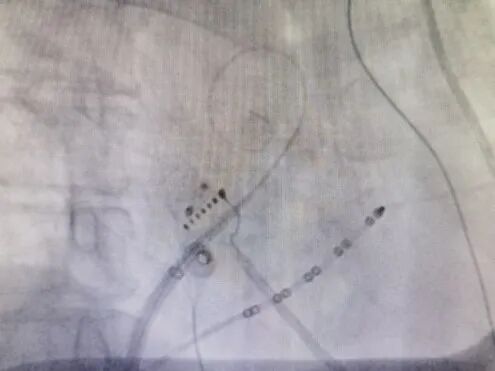

由于穿刺空间极为有限,他们不得不打破常规(通常情况下,射频消融手术需保留两根鞘管配合操作),仅使用单根鞘管在左心房内操作,这无疑是对手术技巧和团队协作能力的巨大考验。但凭借着过硬的专业素养和丰富的临床经验,施主任团队顺利完成了射频消融术和左心耳封堵术,为赵阿姨的心脏健康筑起了一道坚固的防线。

成功完成射频消融术和左心耳封堵术